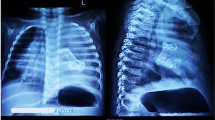

a The child prepared for the surgical removal of the tumor of the right aspect of the cranium, enormously disfiguring the child’s head. b The lung of the “host fetus” with the features of immaturity, atelectasis, and distinct hyaline membranes. Objective magnification ×20. c The autopsy of the child. The large tumor was removed from the cranium of the child but is still attached to the body of its host by a broad strand of fibrovascular “bridge.” The separation of the tumor from the cranial structures of the host child was very easy and it suggests that if not for the cardiorespiratory failure, the chances for a successful operation could have been large. d Especially striking finding was quite well-developed “extremities” of the parasitic fetus

The general autopsy showed that the male newborn has a weight of 3,100 g, with features of fetal respiratory distress syndrome (Fig. 2b). Apart from the head which measures 44 cm in diameter, no other abnormalities in the child’s body were found.